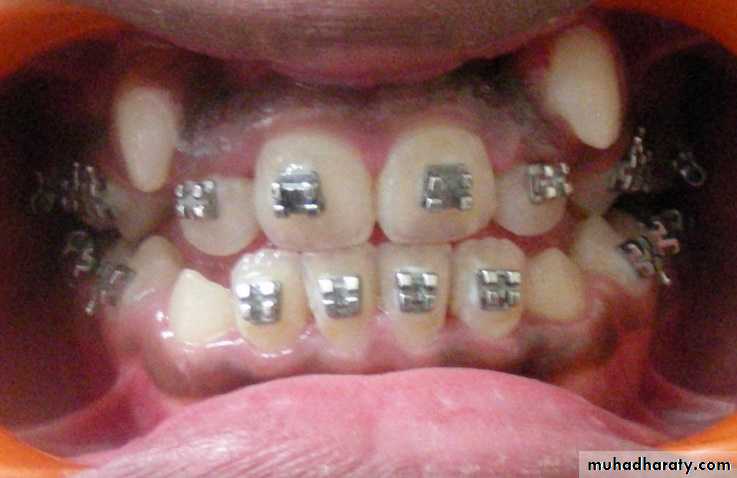

5- Orthodontic reasons :

During the course of orthodontic treatment , tooth or teeth maybe extracted for :a) Therapeutic extraction e.g. extraction of upper 4 . for treatment of malposed upper 3. Extraction of teeth to provide space for tooth alignment .

b) Malposed teeth : teeth which erupted out of line of arch difficult to clean and not amenable for orthodontic treatment are indicated for extraction .

c) Preventive extraction , means that during mixed dentition (permanent and deciduous teeth ) period dental surgeon may extract few deciduous teeth to prevent malocclusion and all these extraction should be done after proper evaluation by specialist expert orthodontic treatment .